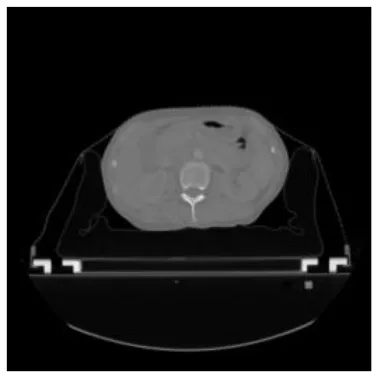

According to the acquired model parameters mentioned above, the testing set was calculated and examined. The performance of the modified algorithm for automatic organ segmentation in CT images is shown in Table 1. The organ contours segmented automatically by the algorithm were similar to those delineated by physicians manually. The model parameters including DSC, Accuracy, Recall, and Precision evaluation ones were served to evaluate the segmentation effectiveness of each organ in the validation and testing sets. In our work, the BCDU-Net CNN algorithm model was used to automatically segment different organs with the different training parameters such as epoch learning rate. The CT images which were randomly selected from the patients were put into the network model for training, and then the contours of different organs which were delineated automatically by the AI technology and manually by medical doctors were evaluated with the similarity coefficients, respectively. The results are given in Table 2. Most of the DSC values were better than 0.85 and among them the best even reached up to 0.9676. Generally, the automatic segmentation results met the requirements of clinical practice.

| Input CT image | Organs with manual segmentation | Organ with automatic segmentation | |

| Bladder | ![]() | ![]() | ![]() |

| Brainstem | ![]() | ![]() | ![]() |

| Eye-L | ![]() | ![]() | ![]() |

| Eye-R | ![]() | ![]() | ![]() |

| Femur-L | ![]() | ![]() | ![]() |

| Femur-R | ![]() | ![]() | ![]() |

| Heart | ![]() | ![]() | ![]() |

| Intestine | ![]() | ![]() | ![]() |

| Kidney-L | ![]() | ![]() | ![]() |

| Kidney-R | ![]() | ![]() | ![]() |

| Liver | ![]() | ![]() | ![]() |

| Lung-L | ![]() | ![]() | ![]() |

| Lung-R | ![]() | ![]() | ![]() |

| Mandible | ![]() | ![]() | ![]() |

| Rectum | ![]() | ![]() | ![]() |

| Spleen | ![]() | ![]() | ![]() |

| Stomach | ![]() | ![]() | ![]() |

The result of manual and automatic organ segmentation.